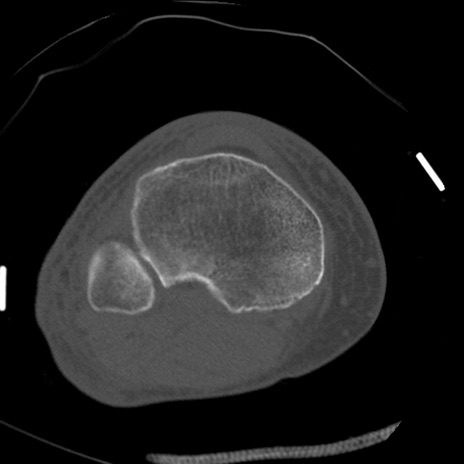

症例28 右膝関節CT(横断像)

右膝関節CT